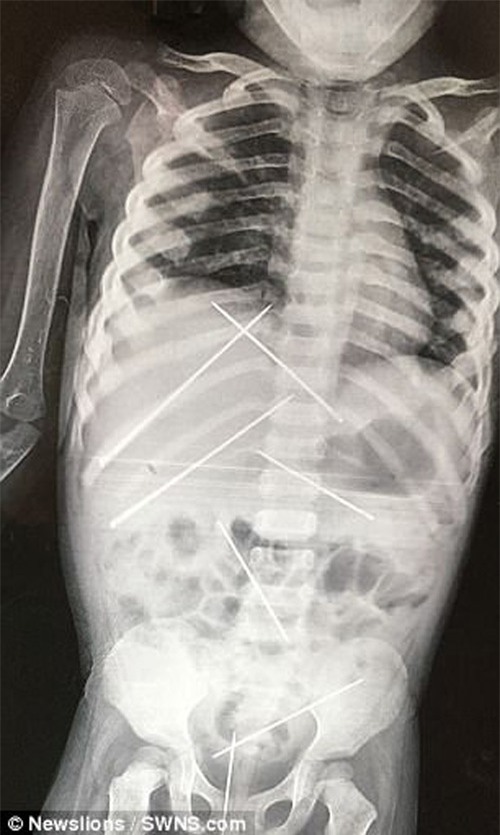

Tại đây, các bác sĩ phát hiện bé bị đâm kim lên nhiều vùng trên cơ thể, trong đó có cả tổn thương vùng kín, India Today đưa tin.

"Có tất cả 7 chiếc kim nằm trong cơ thể bé. Thế nhưng những chiếc kim này không thể lấy ra được vì có thể gây ra cho bé thêm nhiều tổn thương. Bé cần được theo dõi thêm", sau khi thăm khám ban đầu các bác sĩ đã đưa ra kết luận.

Sau 3 ngày, vào ngày 18/7, các bác sĩ mới lấy được hết số kim trong người bé gái. Tuy nhiên, bé cũng đã tử vong ngay sau đó.

7 chiếc kim được lấy ra.